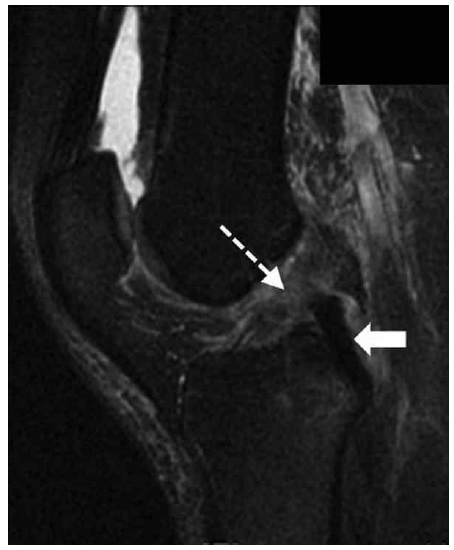

△ 그림 46-8. 추축 이동 골 타박상 패턴

시상면 지방 포화 T2 강조 시퀀스는 외측대퇴골과(점선 화살표)와 후외측 경골 고평부(굵은 화살표)의 전방에서 골부종(높은 신호)을 보이는데, 대퇴골에 대하여 경골의 전방이동이 일어나는 동안 추축 이동 메커니즘의 부위에서의 상호적 골타박상을 암시하는 것이다. 이는 전방십자인대 파열의 가장 간접적인 징후 중 하나이다.

△ 그림 46-9. 전방십자인대의 완전 파열

그림 46-8과 동일한 환자의 시상면 지방 포화 T2 강조영상은 근위와 중간부위에서의 전방십자인대의 부재를 나타냄으로써 완전 파열(점선 화살표)을 암시한다. 후방십자인대의 원위부에서는 정상의 균일한 낮은 신호(굵은 화살표)를 나타냄을 주목